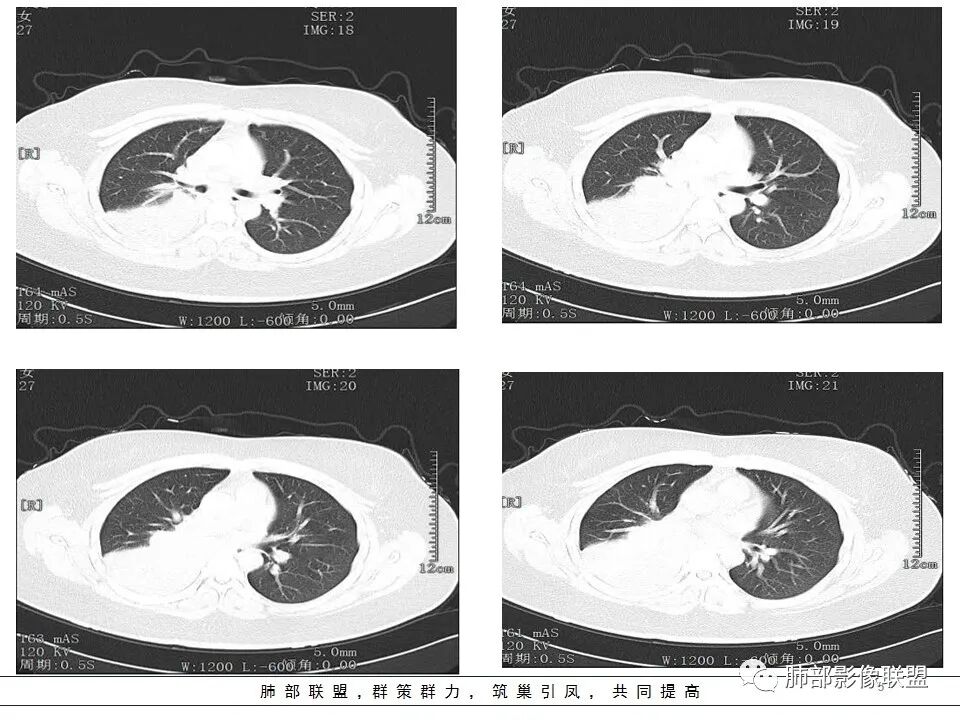

年轻女性,发热6天,咳嗽咳痰三天

CT扫描示右肺下叶支气管堵塞,类圆形大肿块伴胸膜下大片肺实变影,增强扫描类圆形肿块延迟强化,见少量坏死,余实变区增强可见内部血管走行。纵隔见肿大淋巴结。考虑为恶性病变伴右肺下叶肺不张

水晶石头 :

患者青年女性,发热6 天,咳嗽、咳痰3天。为黄脓痰。胸部CT:右肺体积稍小,右中间支气管肿物堵塞,中叶、下叶大片实变不张,与正常肺组织分界清楚。增强实变影明显强化,右下肺支气管近心端见类圆形强化结节影,血管纤细,部分支气管显影变细,纵隔淋巴结肿大。结合无呼吸困难症状,病程长。综合考虑低度恶性病变并阻塞性肺炎,类癌可能大,鉴别结核、淋巴瘤。

右肺体积缩小,右肺巨大低密度肿块并下叶不张,无胸膜尾征,定位肺内,右中间支气管堵塞,肿块内可见粘液栓,不均匀强化,其内血管走行自然,右下肺受侵边缘不整,纵隔内淋巴结肿大,考虑为恶性,年轻女性,粘液表皮样癌首选,其次肉瘤或类癌。

本病例特点是中叶病灶和下叶病灶不一样,支气管腔内的病灶又是怎么样的呢?我们要是有沿支气管重建的冠状位、矢状位会更有利于分析。第一,中叶病灶明显粘液样改变、低密度,且低密度区有占位效应、膨隆,确实要考虑粘液表皮样癌。第二,中叶和下叶支气管显示不出来,但血管显示出来了。中叶病灶血管稀疏、细小,下叶病灶血管粗大、走形正常。朝外肺不张实变,不是单纯的肺不张,肺不张一般体积明显缩小、血管聚拢,该病例肿瘤于其中成分不一样,所以上叶部分病灶考虑为下叶病灶占位效应及膈面向上推压引起,中叶萎缩。综合腔内堵塞、纵隔淋巴结肿大要考虑恶性。

支气管层面位置朝下强化明显,支气管腔内、远端是有差异的,腔内哪些是粘液?哪些是肺组织?是单纯实变?还是合并感染?还是外围都是病变?支气管腔内病变?

该病灶明显实变,需鉴别是内朝外,还是外朝内病变。该病灶内血管走形自然,肺门区血管无明显受压移位,且非起源于胸膜,不张肺组织或者不张肺组织夹杂炎性病变。而非典型肺炎型肺癌及外朝内的其他恶性病变。

1.年轻女性,发热6天,咳嗽咳痰3天。高热伴腹泻。

2.右肺中下叶大片实性密度影,体积有缩小,密度不均,不均匀强化,前份可疑小范围液性密度区。

3.中间段支气管阻塞,腔内隐约见息肉样结节或突入,结节有较明显强化,这很重要,说明它有生命力,强烈提示新生物,而非分泌物或异物等等。

可惜腔内腔外混沌一片,我们不能分辨管壁及管壁外细节,我们不能判断新生物实际大小,不能判断局部支气管彻底破坏还是结节影跨越腔内外。

4.年轻、女性,支气管腔内相关新生物,会想到类癌或涎腺类肿瘤,如粘液表皮样癌等。强化较明显类癌可能性较大。支气管鳞癌和间叶组织肿瘤的可能性都非常小。

5.如此大范围实性密度影,结合高热临床表现,阻塞性肺炎诊断应当是成立的。病灶内梭形液性密度区,未见强化,符合炎性分泌物。